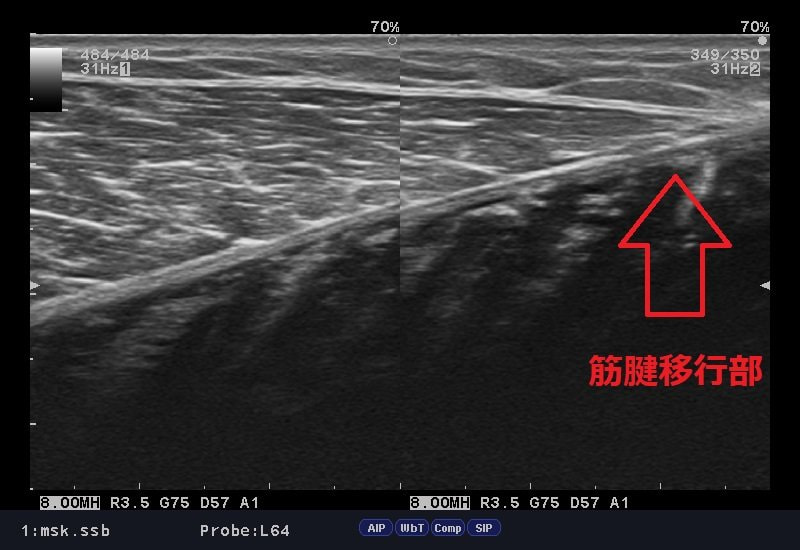

下のエコー画像、ふくらはぎの筋腹内にも腫れが残っていますが、筋腱移行部ラインが不明瞭となっております。

これは肉離れの兆候となっており、まだ組織が修復されていないサインでもあります。

エコー検査は筋肉の状態を正確に確認でき、的確に治療をできます。